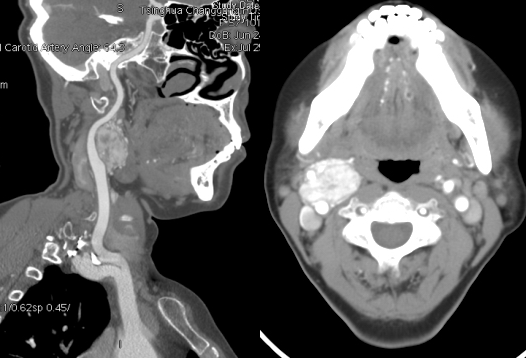

图3 CTA(左)、DSA(右)可精确诊断颈动脉体瘤,判断肿瘤大小及血供。

发现颈部肿物后,颈部超声可作为首选无创检查。颈动脉造影(DSA)为诊断“金标准”,造影可见颈动脉分叉增宽呈杯口状,瘤体内有丰富的细小滋养血管。随着数字技术的进步完善,CT血管造影(CTA)已成为几与DSA相媲美的血管疾病诊断技术。